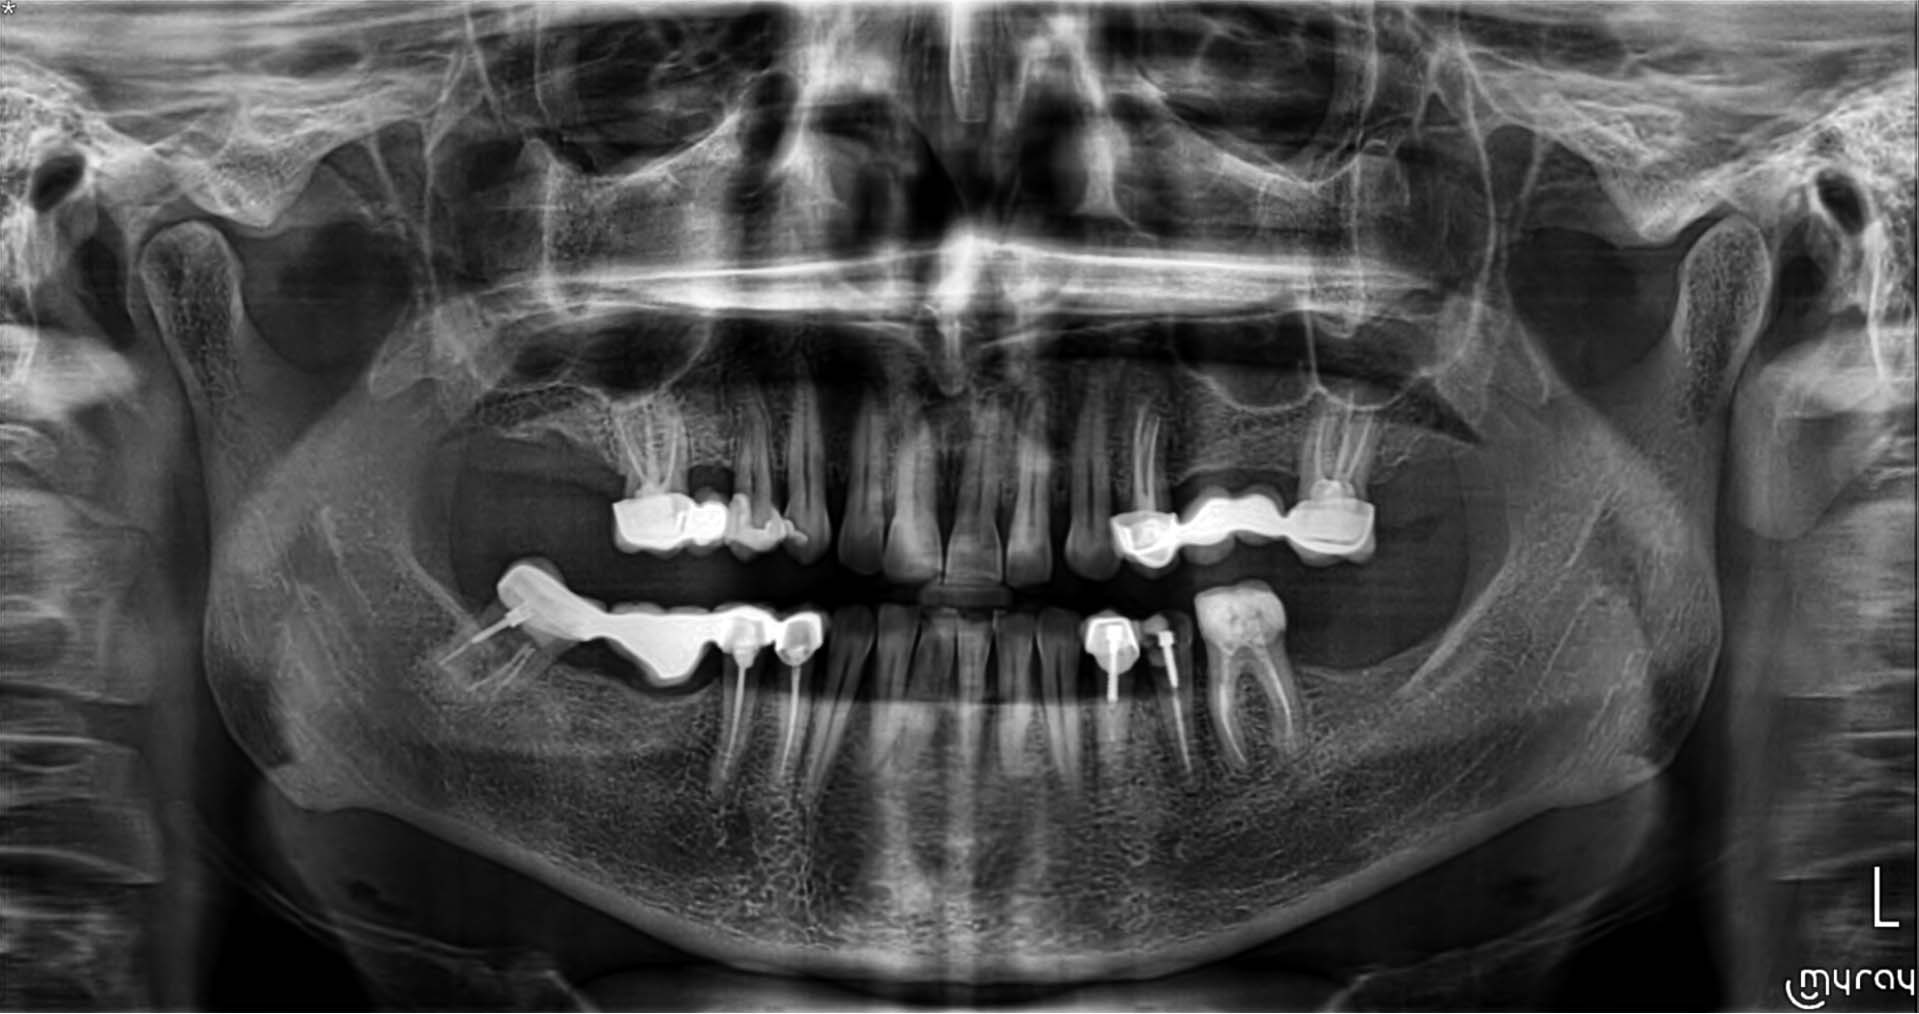

• Radyo-opak yansımaları ortadan kaldıran özellik • Doldurulmuş kanal yansımaları eleminasyonu • İmplant yansımaları eleminasyonu • Amalgam ve restorasyon yansımaları eleminasyonu

10x10 fov alanı üçüncü molar kökler ve sinüs tabanları dahil, çevresindeki anatomik özelliklerin yüksek doğrulukta taranması, doğru teşhis ve iyileştirilmiş tedavi planlaması için yararlıdır. X5 10 x 10cm fov alanını 80 μm luk detaylarla vermektedir.

İmplant bölgesini çevreleyen anatomik yapılar hakkında bilgi verir. Kemik kalitesinin değerlendirmesi ve gelişmiş IRYS yazılım özelliğiyle cerrahî prosedürlerin, ameliyat sonrası iyileşme sürelerinin en iyi şekilde planlanması mümkün olur. Bu özellik sayesinde geniş kapsamlı yazılımın implant kütüphanesinde bulunan implantların seçilip konumlandırılarak görüntüler üzerinde planlama yapılabilir.